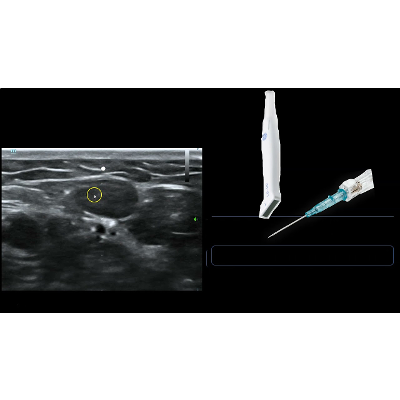

Ultrasound Guided IV Access (Presentation)